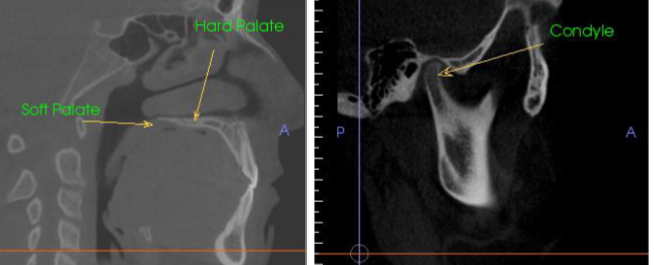

what is this showing for the CBCT

volumetric rendering

bilateral view of TMJ

What CBCT view is presented, and what type of contrast is shown on the right ?

sagittal; high